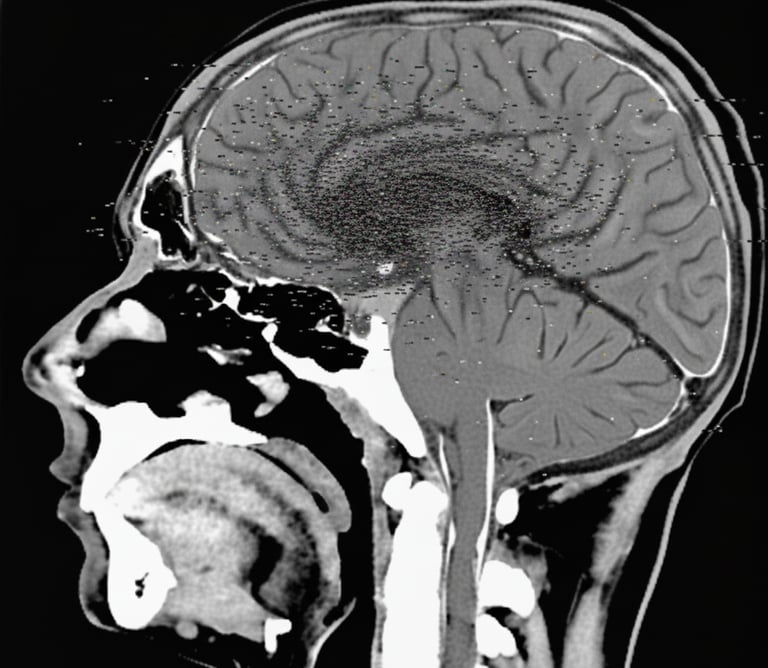

pht. 1936 (Ankara GATA Hastanesi'nde çekildi.)

Beynin frontal lobundan parietal lobuna kadar uzanabilen parazit bir tümör beyin kıvrımlarını değiştirip OÇ şeklini almasıyla hastada belli başlı belirtiler ortaya çıkarabilir.